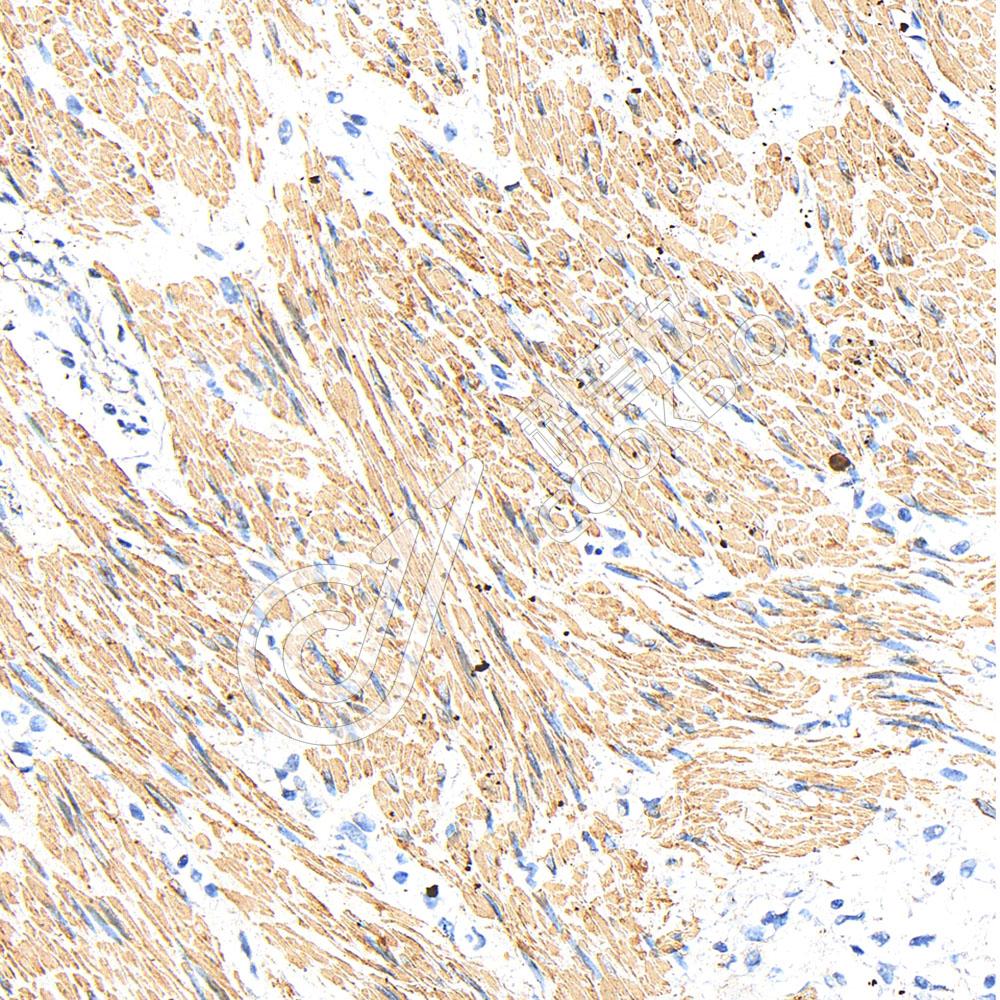

IHC检测ATP5A蛋白(货号 K5460365).

样品: 人肺癌, 4%多聚甲醛 (货号KSG1101) 固定12-24小时.

抗原修复: Tris-EDTA抗原修复液(pH 9.0) (KSG1203), 100℃, 25分钟.

—抗: 1: 2000稀释, 4℃ 孵育过夜.

二抗: S-vision免疫组化多聚二抗(山羊抗小鼠), 即用型(货号KB3903), 室温孵育20分钟.